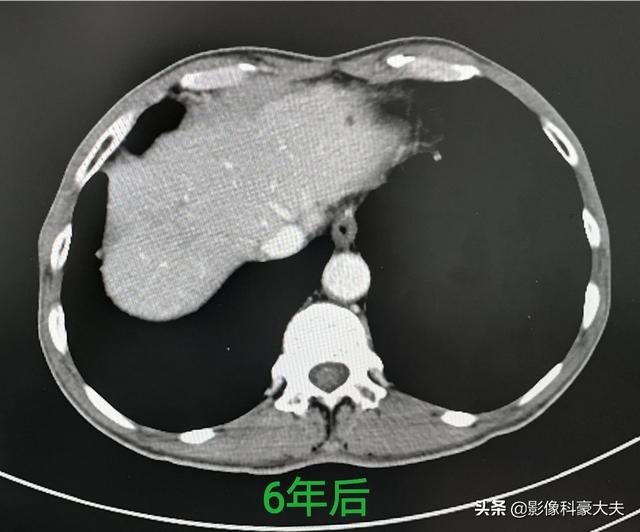

这位病人手术已经6年了,因为发现及时,手术完整切除,恢复很好没有复发:

已经在一年前做了手术切除,上周复查恢复很好: